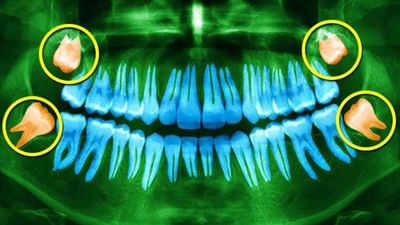

વેબએમડીના રિપોર્ટ અનુસાર, એક પુખ્ત વ્યક્તિના કુલ 32 દાંત હોય છે. તેમાંથી, 4 (બે ઉપર અને બે નીચે) ડહાપણના દાંતમાંથી બહાર આવે છે. આ ડહાપણની દાઢ ચારેય ખૂણામાં છેલ્લી છે. તેઓ માનવ બુદ્ધિ સાથે સંકળાયેલા છે કારણ કે તેઓ 17 થી 21 વર્ષની વય વચ્ચે ઉગી આવે છે, પરંતુ સંશોધન એ પણ સાબિત કર્યું છે કે તેમના કારણે બુદ્ધિનું વધવાને કોઈ સંબંધ નથી.